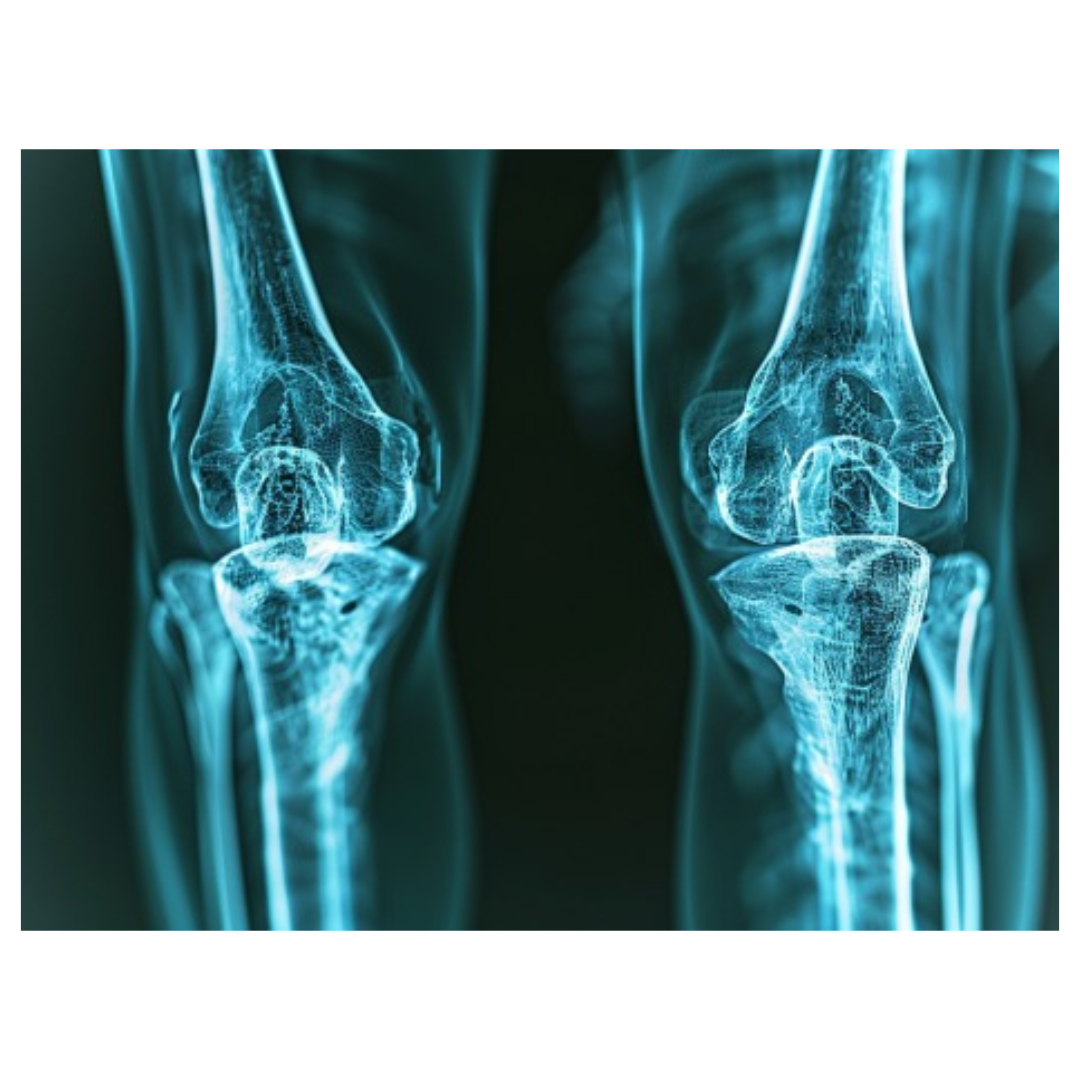

3. 기능 상실

관절이 완전히 손상되면 더 이상 움직일 수 없게 됩니다. 관절 내 연골이 닳아 없어지거나, 뼈가 직접 맞닿는 상황까지 이르기도 하며, 이로 인해 심한 통증과 함께 기능 상실이 발생합니다.